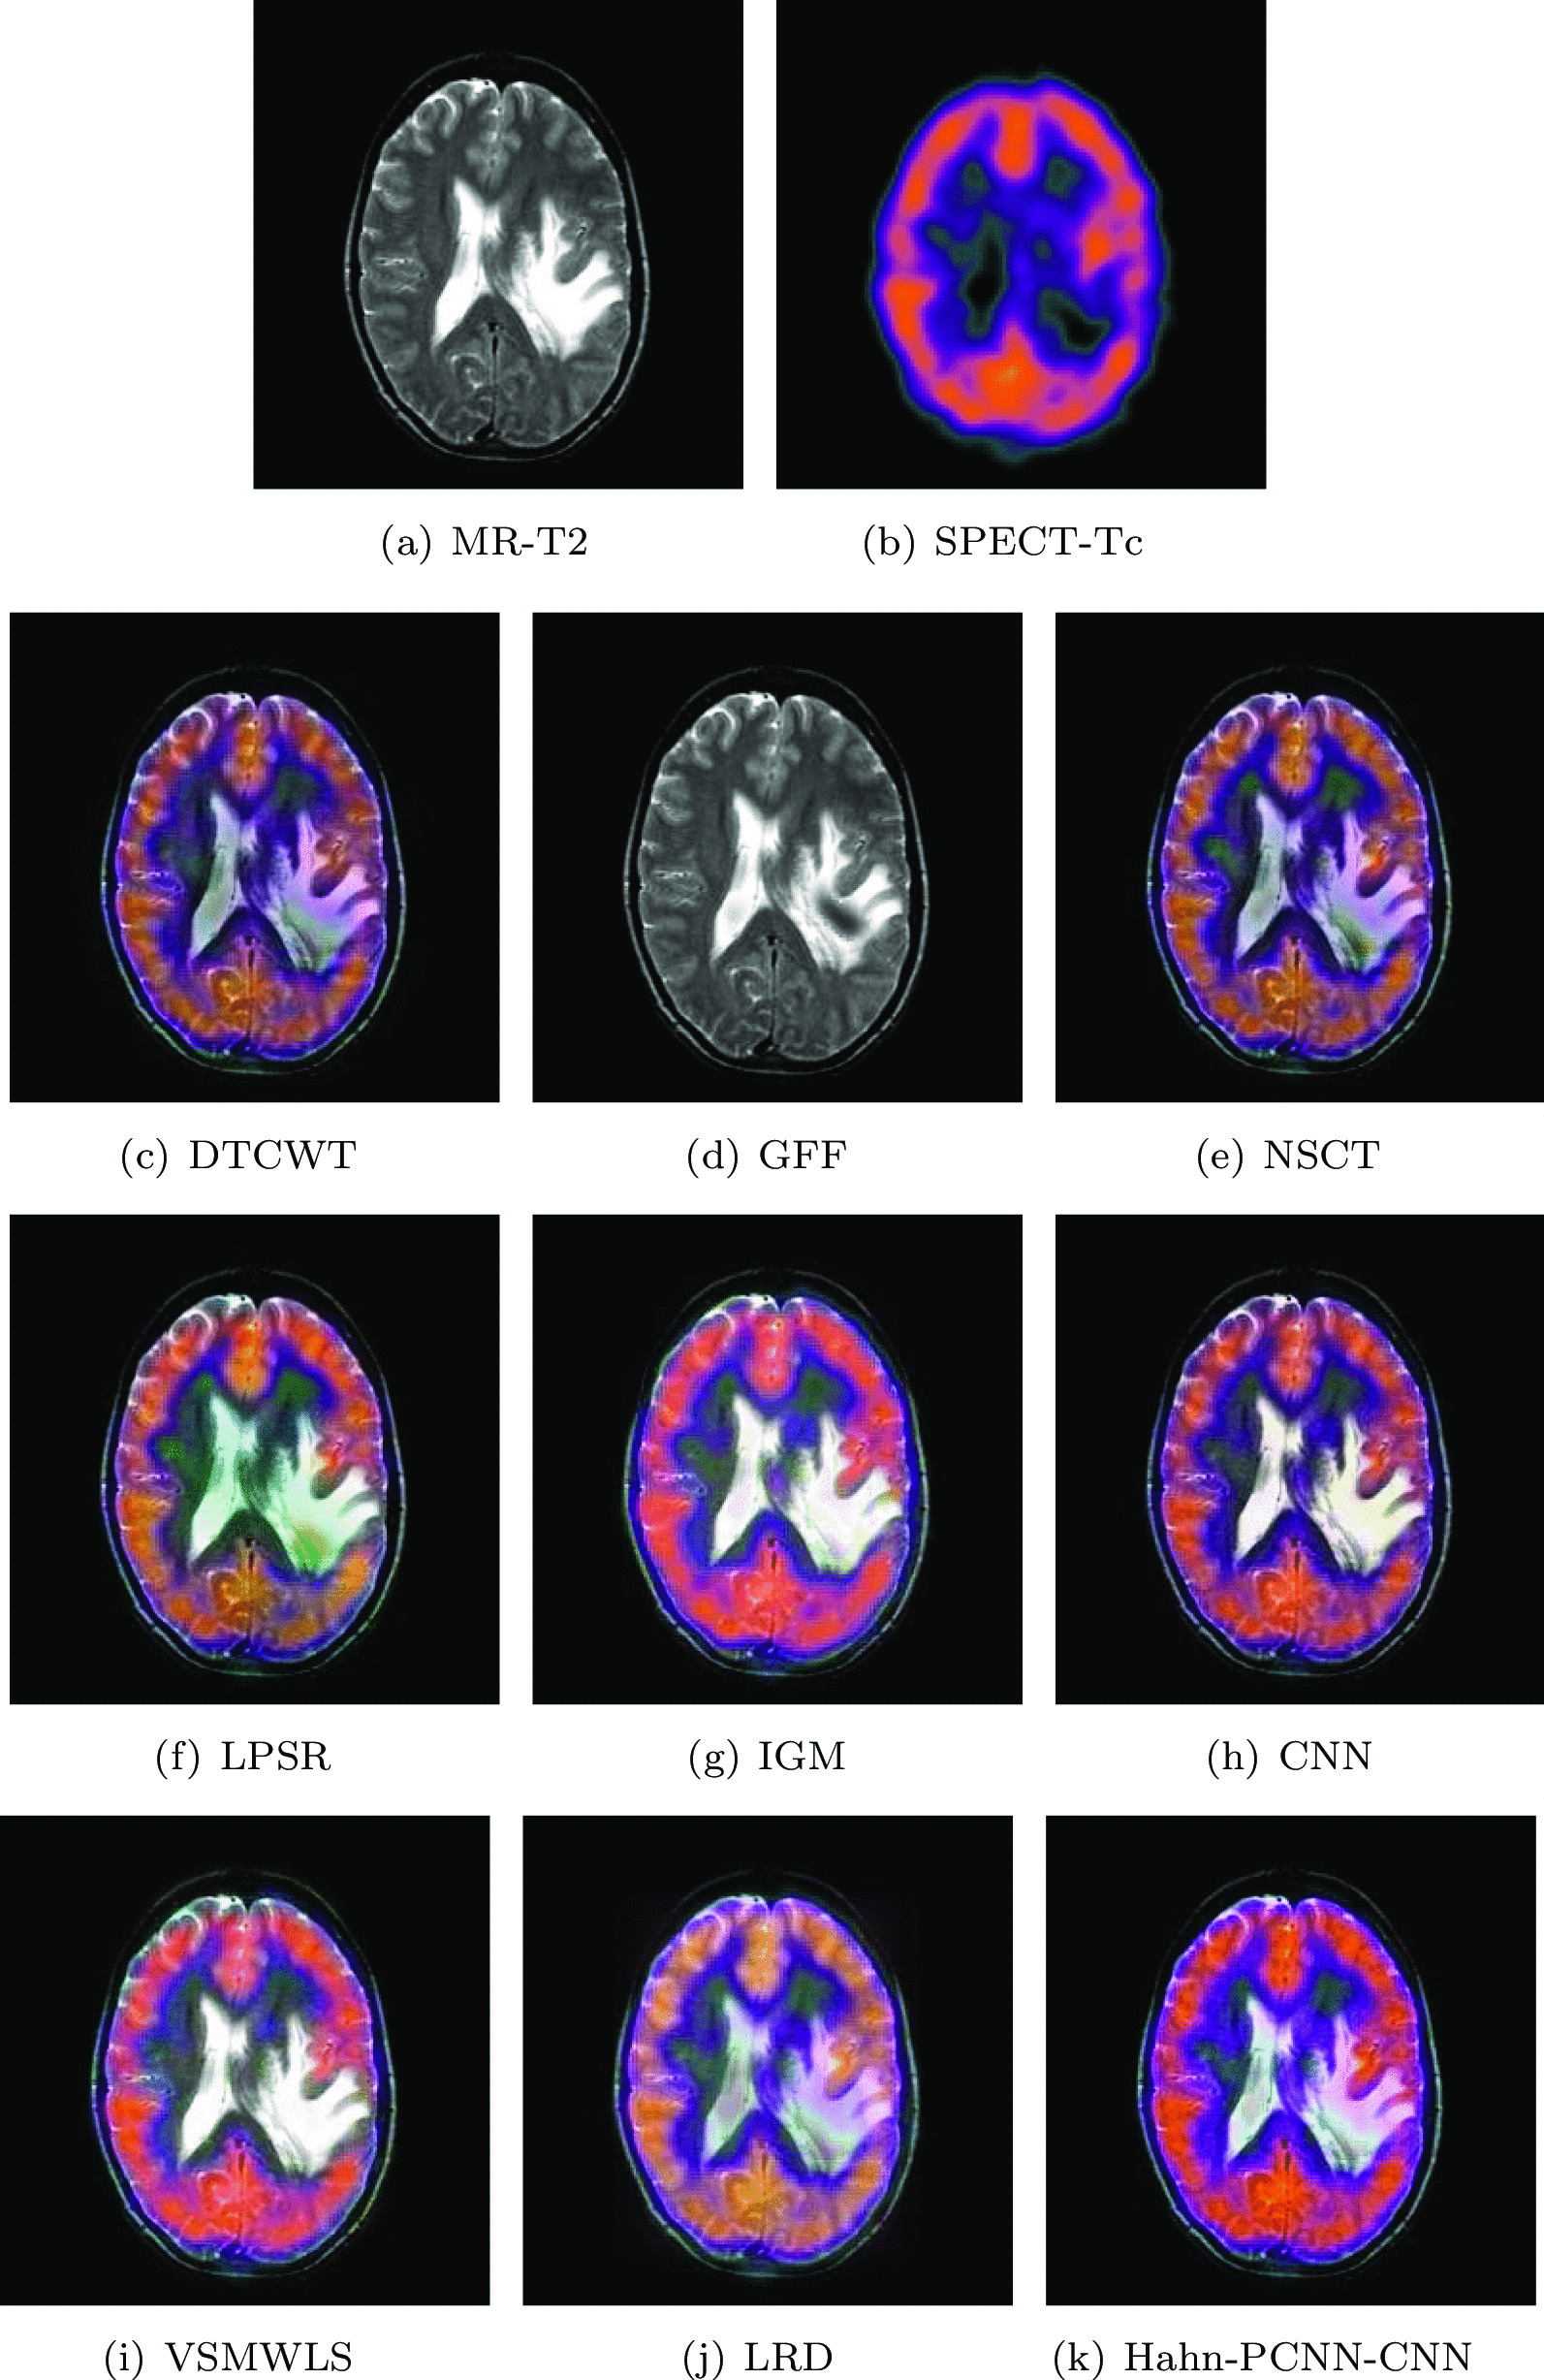

Mild Alzheimer’s disease

The source images in Figs. 10 and 11 are from a 70-year-old man. He suffers from memory loss and is always depressed, which is a manifestation of mild Alzheimer’s disease. In the MR-T2 image, the global hemispheric sulcus is enlarged and is more prominent in the parietal lobe; in PET-FDG images, local brain metabolism is abnormal, especially in the anterior and posterior regions of the parietal wall of the temporal lobe. Changes have also occurred on both sides of the temporal lobe. Ideally, the above-mentioned information is included in the fused image and at the same time, interference information items are eliminated. The color distortion of the fused image obtained based on GFF and LPSR algorithms will affect the expression of metabolism; the brightness of the fused image obtained by IGM and VSMWLS algorithms is too high, resulting in unclear structural information; the brightness of the fused image obtained based on DTCWT and NSCT algorithms is too dark, resulting in unclear edges of the caudate nucleus; the fused image obtained by CNN and LRD algorithms retain the effective information of the source image, but the color saturation is poor; the fused image obtained based on the Hahn-PCNN-CNN algorithm realizes the perfect fusion of the source image, both in terms of structural information and metabolism. At the same time, it also performs well in terms of chroma and saturation and the image is easy to observe. Tables 9 and 10 show the objective performance of all algorithms. It can be seen that the Hahn-PCNN-CNN algorithm is superior to other algorithms in all metrics.

Fig. 10.

The first set of fused MRI-PET images from 9 methods on mild Alzheimer’s disease

Fig. 11.

The second set of fused MRI-PET images from 9 methods on mild Alzheimer’s disease